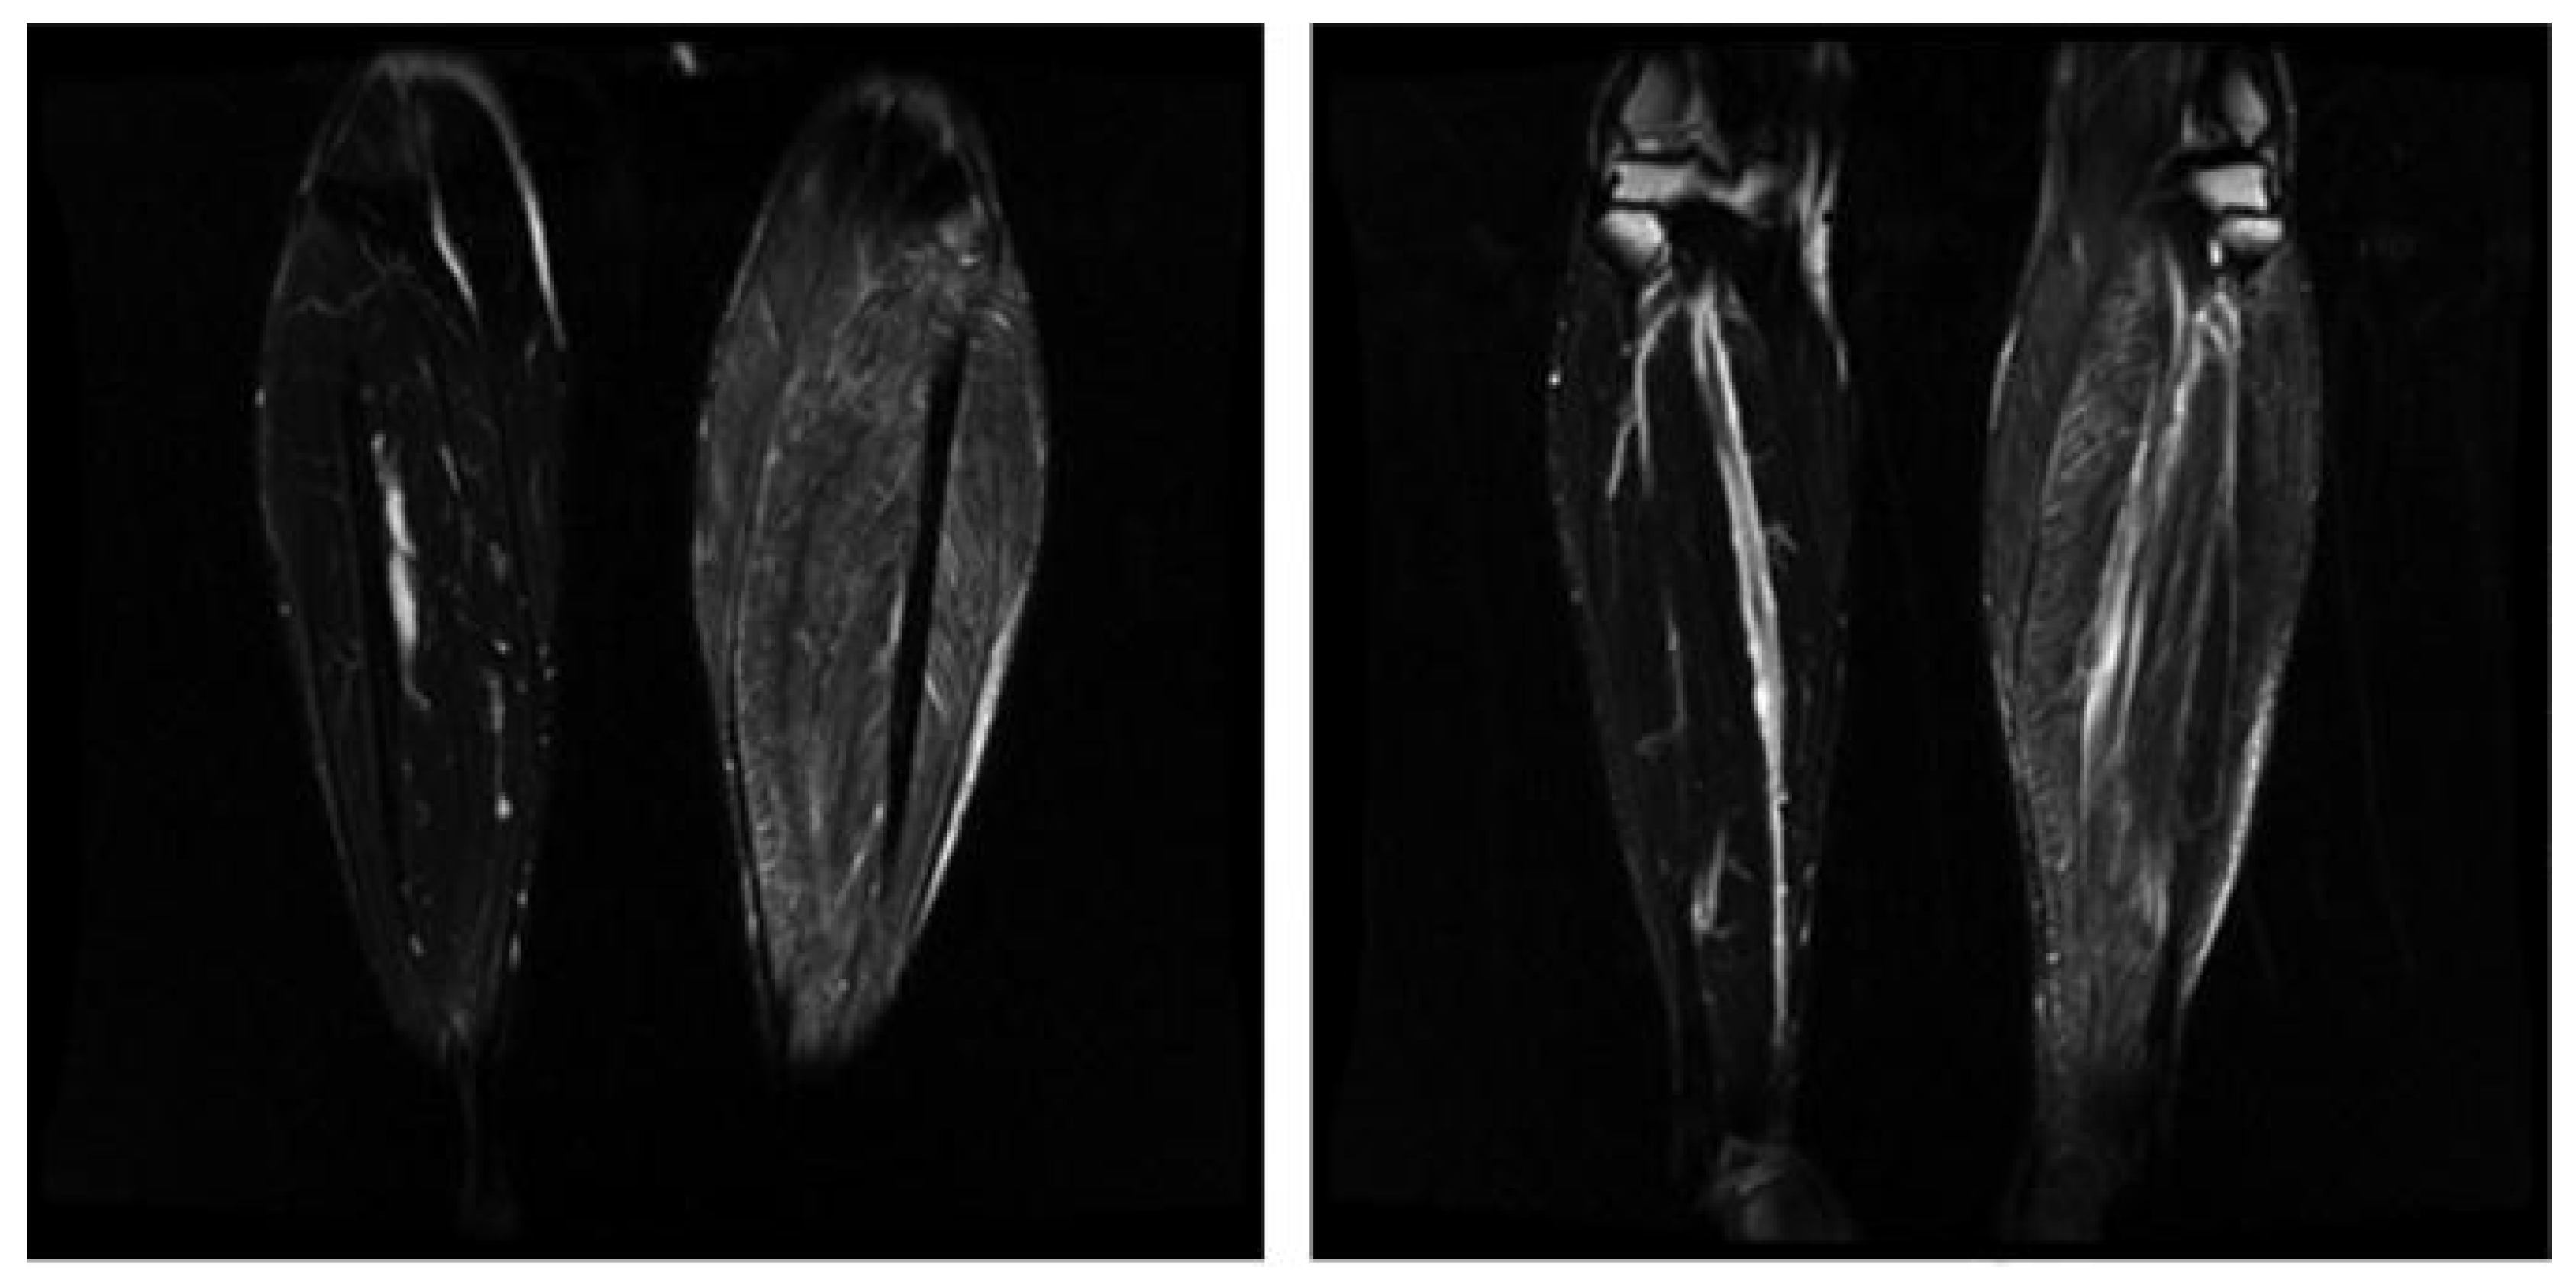

- Figueroa-Bonaparte, S.; Segovia, S.; Llauger, J.; Belmonte, I.; Pedrosa, I.; Alejaldre, A.; Mayos, M.; Suárez-Cuartín, G.; Gallardo, E.; Illa, I.; et al. Muscle MRI Findings in Childhood/Adult Onset Pompe Disease Correlate with Muscle Function. PLoS ONE 2016, 11, e0163493. [Google Scholar] [CrossRef] [PubMed]